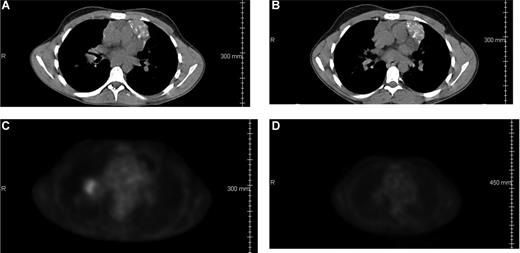

Patient 2517 had failed a prior autologous transplantation for primary refractory HD before undergoing a matched related donor allo-HCT. His disease relapsed within 6 months of the transplantation. He was treated with gemcitabine monotherapy followed by DLI. However, there was evidence of disease progression within 2 months of DLI. The patient had evidence of PET-avid right hilar adenopathy immediately before receiving ipilimumab at 3.0 mg/kg. CR was achieved on the 1-month reassessment after ipilimumab (Figure 3). The CR has been durable for 37 months at the time of this report.

Regression of malignancy in a patient with HD. CT scans (A,B) and PET scans (C,D) from patient 2517 (dose level 3.0 mg/kg) showing right hilar adenopathy before (A,C) and 2 months after (B,D) ipilimumab infusion.